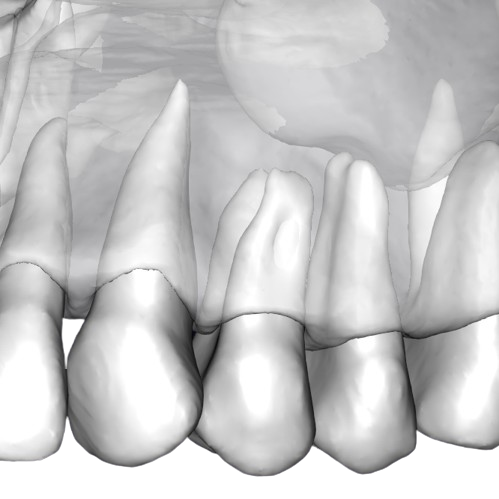

Об’єм: 10×10 см

1100₴

Призначається для діагностики стану всіх зубів, кісткової тканини верхньої та нижньої щелеп.

Записатися Детальніше

Об’єм: 10×6 см

800 ₴

Призначається для діагностики стану зубів, а також кісткової тканини верхньої щелепи.

Записатися Детальніше

Об’єм: 10×6 см

800 ₴

Призначається для діагностики стану зубів, а також кісткової тканини нижньої щелепи.

Записатися Детальніше